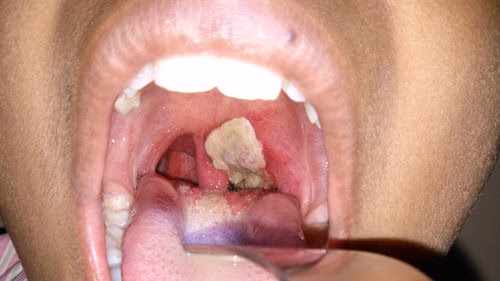

- Xuất hiện giả mạc trắng ở mặt sau hoặc 2 bên thành họng.

Bệnh bạch hầu thường gặp với những triệu chứng điển hình như sốt nhẹ, đau họng, ho, khàn tiếng, chán ăn. Sau 2-3 ngày xuất hiện những biểu hiện trên thì giả mạc mặt sau hoặc hai bên thành họng, có màu trắng ngà, xám hoặc đen. Giả mạc dai, dính, dễ chảy máu.